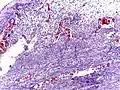

Pathology

Even for clinically certain appendicitis, routine histopathology examination of appendectomy specimens is of value for identifying unsuspected pathologies requiring further postoperative management.[61] Notably, appendix cancer is found incidentally in about 1% of appendectomy specimens.[62]

Pathology diagnosis of appendicitis can be made by detecting a neutrophilic infiltrate of the muscularis propria.

Periappendicitis (inflammation of tissues around the appendix) is often found in conjunction with other abdominal pathology.[63]

Micrograph of appendicitis and periappendicitis. H&E stain

Micrograph of appendicitis showing neutrophils in the muscularis propria. H&E stain

Acute suppurative appendicitis with perforation (at right). H&E stain